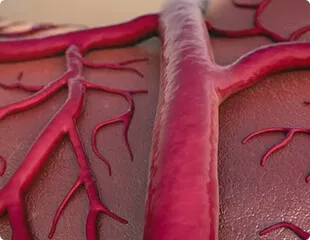

उच्च रक्तचाप में संवहनी सफाई क्यों महत्वपूर्ण है

अवरुद्ध रक्त वाहिकाएं भंगुर हो जाती हैं, जिससे आँतरिक अंगों का विघटन होता है।

Cartiofin कार्डियोवास्कुलर सिस्टम को नियंत्रित करने और रक्त वाहिकाओं को मजबूत करने में मदद करता है।

धमनी (Arterial) की जटिल संरचना कोलेस्ट्रॉल प्लेक की दीवारों को मजबूत करने और उनकी लोच को बहाल करने में मदद करती है।

रक्त वाहिकाओं को साफ करने के सामान्यीकरण में योगदान देता है।